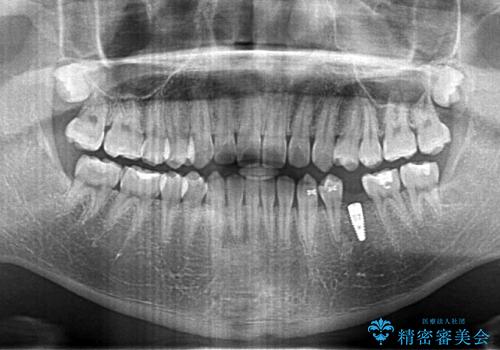

- 左下の奥歯が生まれつき歯が少ない患者様です。

歯がなかった時期に隣の歯が移動してすき間があったため、部分的な矯正治療を行い、インプラントを入れるすき間を確保しています。

- 68.2万円 内訳: 部分矯正治療 22万円、インプラント 22万円、チタンカスタムアバットメント11万円、ジルコニアクラウン 11万円、矯正用シリンダーテック(仮歯) 2.2万円費用は治療当時の料金となります

通常矯正治療は後戻りがあるので保定が必要です。

しかし、今回は不要でした。

矯正治療で歯を移動して得られたすき間はインプラントのクラウンで動かないようにできるためです。

保定が不要という点におきましては、部分矯正と補綴(被せ物)治療は非常に相性がよく、得られるメリットも大きいといえます。